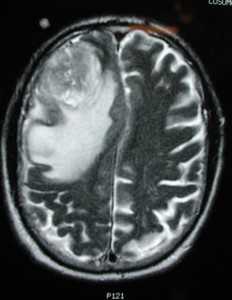

Глиобластома: симптомы, выявляемые с помощью МРТ. Аксиальный срез в режиме Т1 после контрастирования препаратом гадолиния демонстрирует распространенную опухоль правой лобной доли. Изображение предоставлено доктором George Jallo.

МРТ того же пациента. Т2-взвешенное изображение демонстрирует то же поражение, что и на предыдущем рисунке с заметным отеком и смещением срединных структур. Эти находки соответствуют высокой степени злокачественности опухоли.

Как выглядит глиобластома на МРТ? Как правило, образование на томограммах представляет собой зону, имеющую в основном пониженный сигнал на Т1-взвешенных изображниях и повышенный сигнал на Т2- взвешенных изображениях. Могут присутствовать внутренние кистозные участки, участки потери сигнала, обусловленные крупными сосудами, внутренние зоны повышенной интенсивности сигнала на Т1-ВИ (геморрагические очаги), новообразованные сосуды, очаги некроза, обширный перитуморозный вазогенный отеком и значительный масс-эффект. Также может выявляться неравномерное, но интенсивное накопление контрастного вещества на основе гадолиния (та же картина наблюдается на КТ после введения йодсодержащего контраста), как в основной опухоли, так и в метастатических очагах, характерных для МФГ. МРТ более чувствительна к этим изменениям, чем КТ.